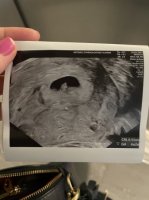

Vi kunne ikke se noe på mandag så her går det rett vei mener de. Hcg øker som det skal og hadde 4100 igår, hvordan er dine? Jeg har time igjen neste uke jeg og, antar han bare er slow starter som broren varAkkurat slik var det hos meg også på mandag. Var også 5+5 da. Fikk UL på grunn av blødninger. Og den så ganske lik ut som hos deg. En fostersekk i livmoren, men ikke så mye mer å se.